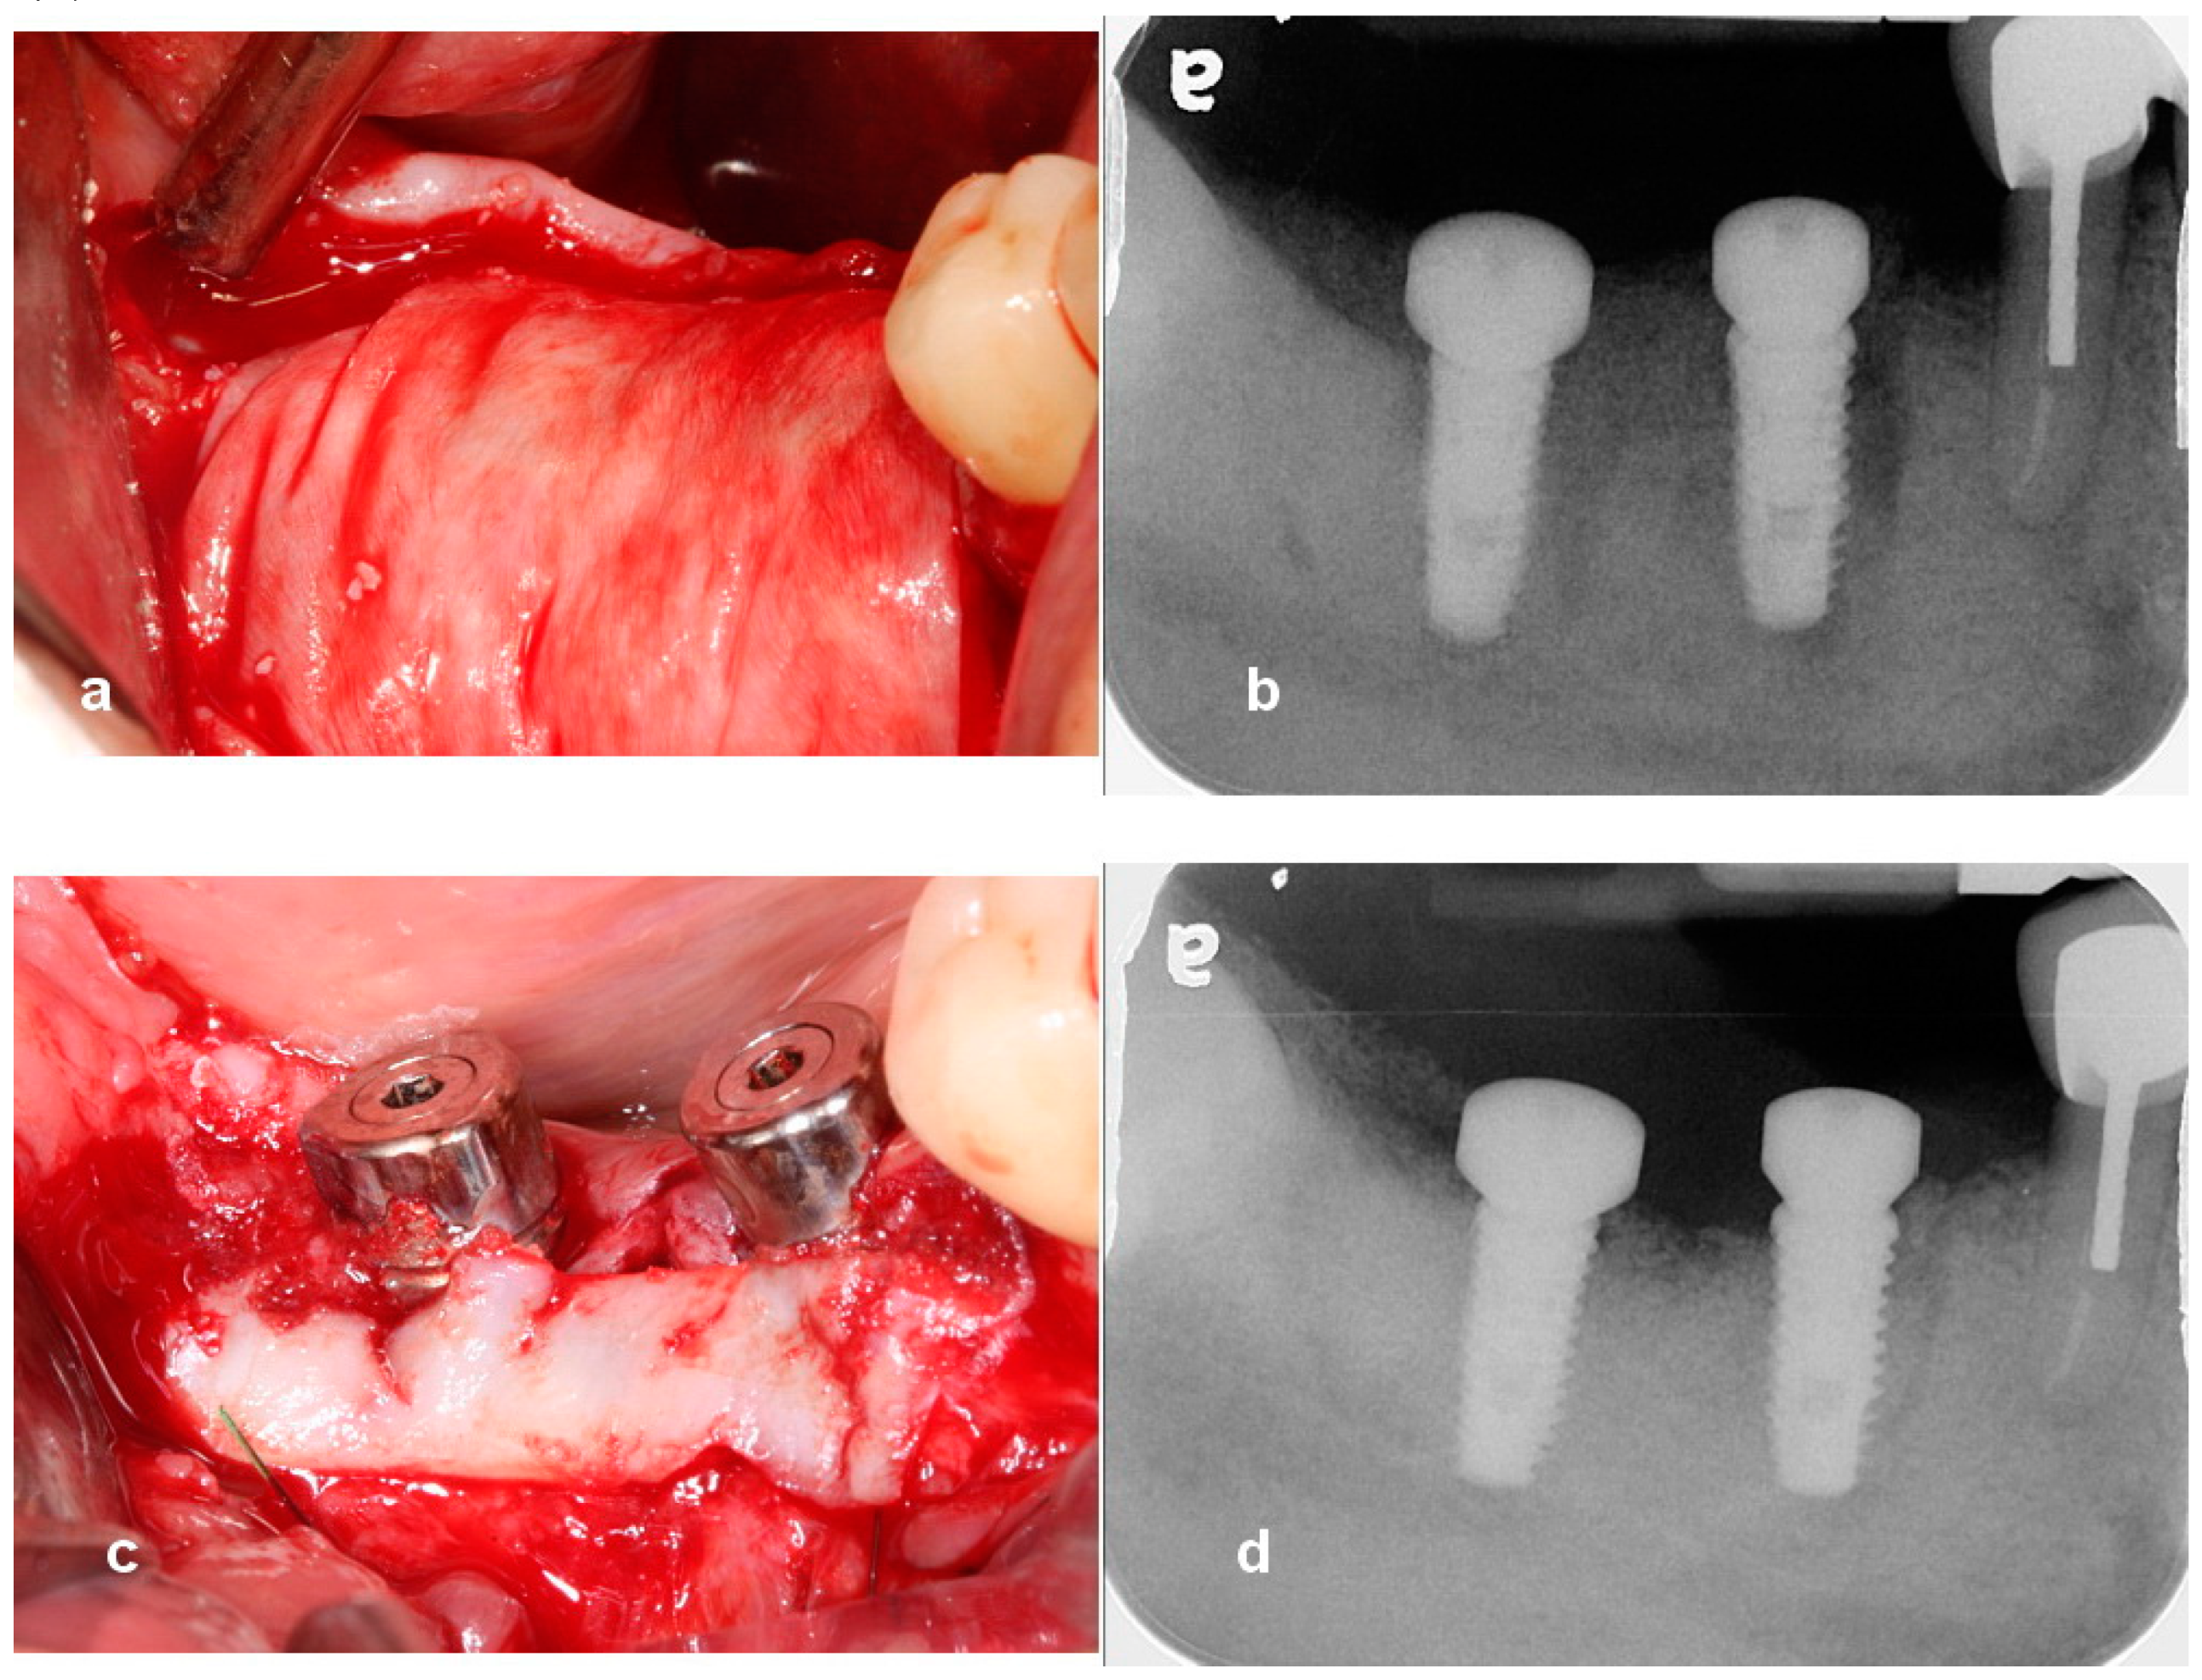

Utilization of Tenting Pole Abutments for the Reconstruction of Severely Resorbed Alveolar Bone: Technical Considerations and Case Series Reports

2. Case Presentations